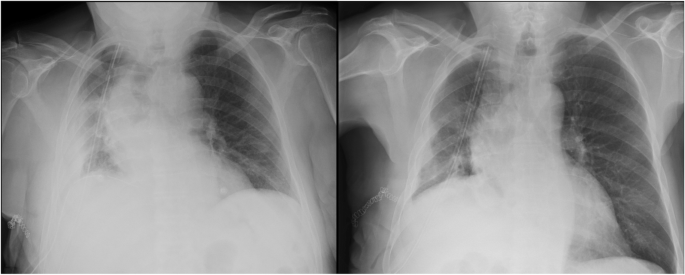

For PE, it is known that Chest US can represent the gold-standard technique [18,19,20]. Inter-rater agreement with Chest X-ray showed a fair magnitude. Seven cases of discordance have been reported. It is not surprising that Chest US was able to identify 6 cases that chest X-ray missed. Pleural effusions, also minimal amounts, are well detected by ultrasounds. Only in one case chest X-ray reported loculated PE in disagreement with US. In this case, chest US was confident for lung consolidation, for instance obstructive atelectasis. The patient underwent multiple bronchoscopies to remove obstruction by secretions. Figure 2 reported chest X-ray performed pre- and post-bronchoscopies. In our sample chest US confirmed to be referral technique for PE as already reported in literature.

Chest x-ray performed before (on the right) and after (on the left) bronchoscopy. Chest x-ray reported the presence of loculated pleural effusion, which was correctly identified as obstructive atelectasis by Chest US (see Fig. 4)

The same case of Fig. 2. Chest US reported LC compatible with obstructive atelectasis and reduction of volume of the hemithorax. Chest X-ray was required for a panoramic view